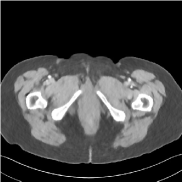

Refer to caption FBPRMSE = 194.09 HURefer to caption FBPRMSE = 194.09 HURefer to caption PWLS-ULTRARMSE = 43.40 HURefer to caption PWLS-ULTRARMSE = 43.40 HU

Refer to caption FBPConvNetRMSE = 34.24 HURefer to caption FBPConvNetRMSE = 34.24 HURefer to caption SUPER-FCN-DataTermRMSE = 31.21 HURefer to caption SUPER-FCN-DataTermRMSE = 31.21 HU

Refer to caption SUPER-FCN-ULTRARMSE = 28.82 HURefer to caption SUPER-FCN-ULTRARMSE = 28.82 HURefer to caption ReferenceRefer to caption Reference

Figure 5: Reconstructed images of slice 150 of patient L192 using of FBP, PWLS-ULTRA, FBPConvNet, SUPER-FCN-DataTerm, and SUPER-FCN-ULTRA, respectively, shown along with the reference.

Fig. 5 shows reconstructions using FBPConvNet, SUPER-FCN-DataTerm (i.e., β=μ=0𝛽𝜇0\beta=\mu=0), PWLS-ULTRA, and SUPER-FCN-ULTRA, respectively. For SUPER-FCN-DataTerm, when optimizing the data-fidelity term, we start with the deep network’s output and ran 5 iterations for the data-fidelity term to avoid overfitting to the analytical FBP images. In Fig. 5, obviously, FBPConvNet significantly suppresses noise and artifacts compared to PWLS-ULTRA, but it also over-smooths many details (e.g., features in the zoom-in box) in the reconstruction. SUPER-FCN-DataTerm, by enforcing data consistency, helps reduce overfitting issues and reconstructs image details and tissue boundaries better compared to the standalone FBPConvNet. Our SUPER-FCN-ULTRA method, however, exploits richer prior information (via the union of learned sparsifying transforms) and explicit network regularizer and outperforms the SUPER-FCN-DataTerm approach. Additional such comparisons for other selected test slices are included in the supplement (Fig. 15).